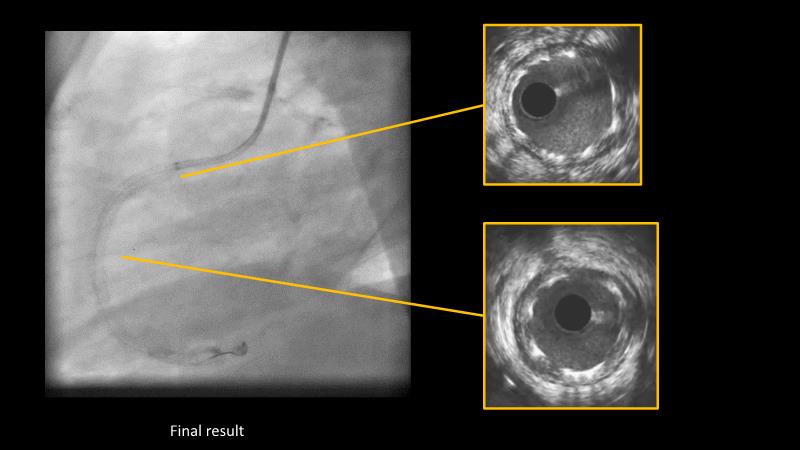

Making treatment and management of complex PCIs easier with Cre8 EVO

Maximize patient clinical outcomes in complex percutaneous coronary interventions (PCIs) by joining this session. Discover how accurate patient evaluation, advanced imaging/functional modalities, optimized procedures, and the Cre8 EVO device contribute to improved safety and efficacy, and review the challenges associated with DES implantation in complex PCIs.

- To understand how the Cre8 EVO unique technology and its specific design may contribute to improve the procedural success and clinical outcome of complex PCIs in complex patients